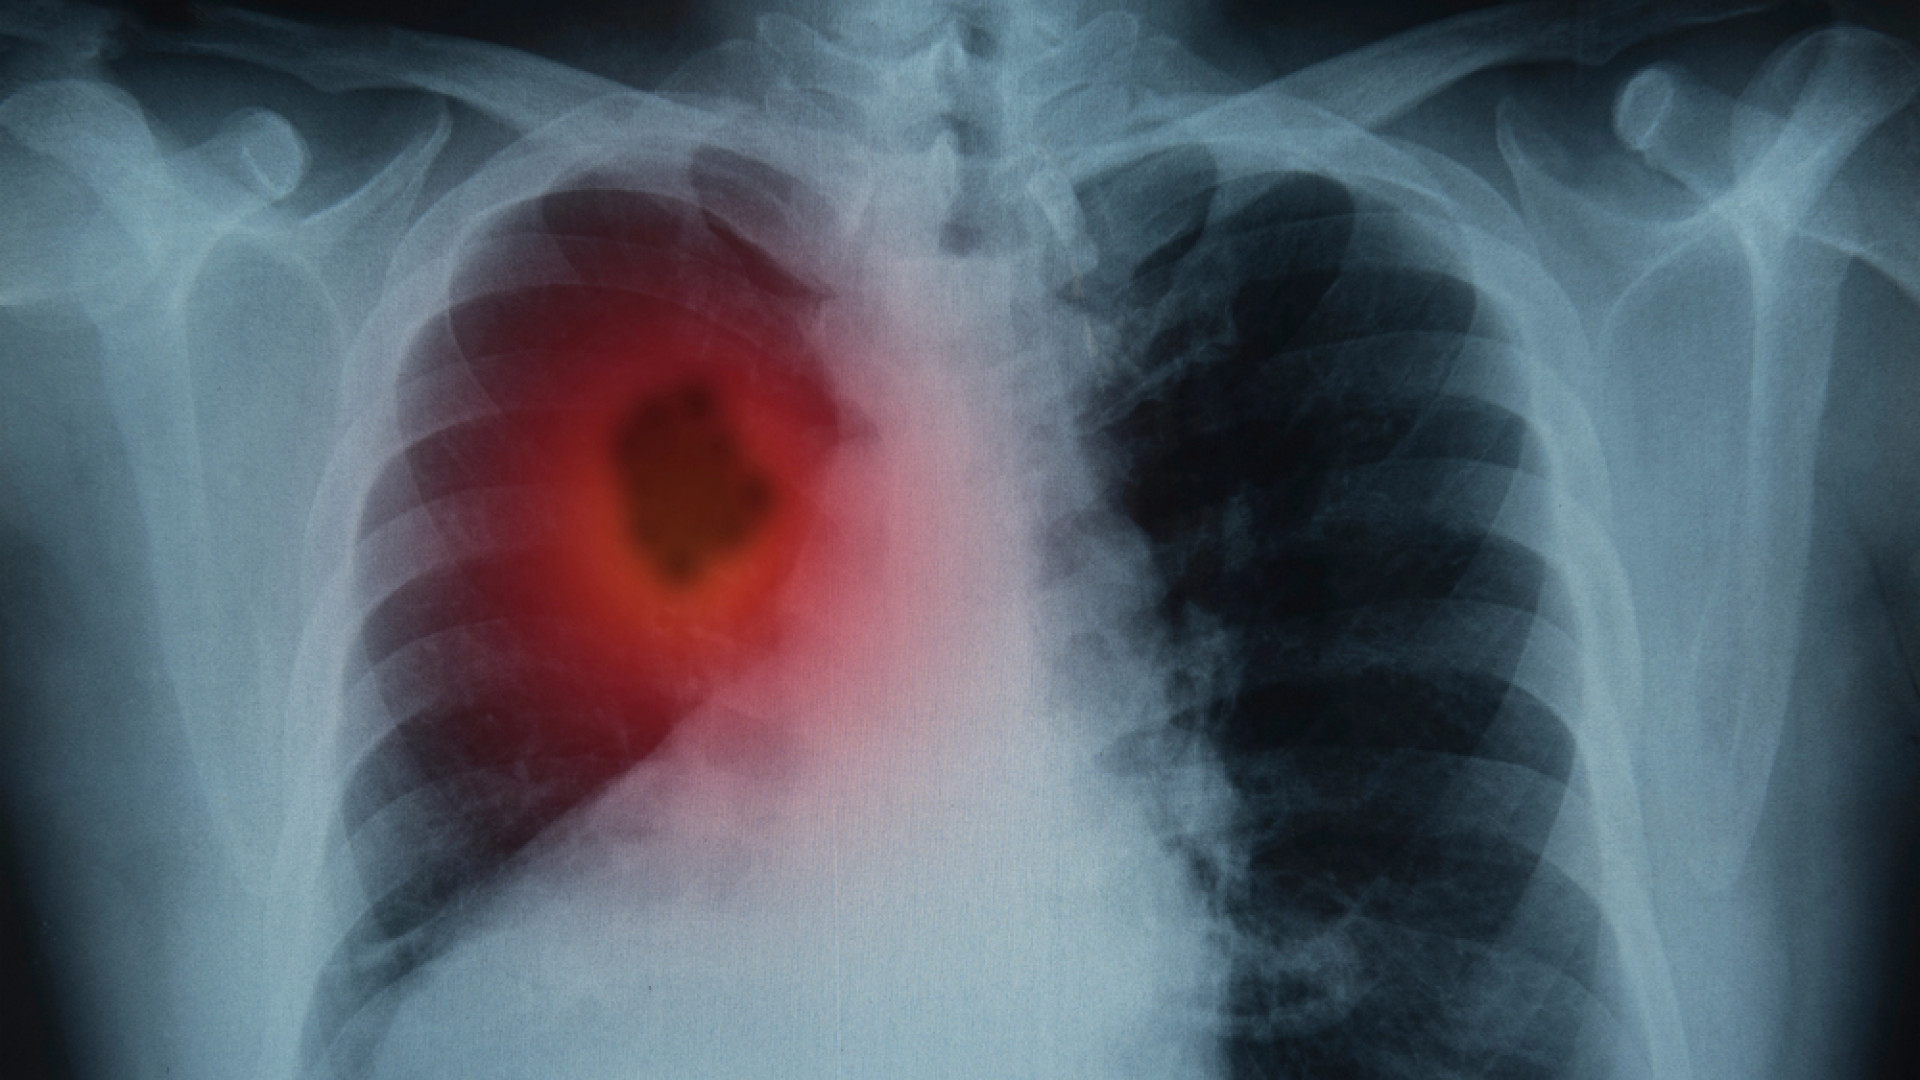

Врач назвал эффективный способ выявления рака легкого

Рак легкого является одним из наиболее агрессивных онкологических заболеваний, но для его диагностики существует действенный метод - НДКТ-скрининг, способный спасти миллионы жизней. Об этом в интервью "Ленте.ру" рассказал заслуженный врач, профессор Петр Яблонский, передает TengriHealth.

Специалист пояснил, что сложность выявления онкологических заболеваний легких обусловлена отсутствием нервных окончаний в нижних отделах дыхательной системы. Поэтому заболевание может долгое время протекать бессимптомно, а отдельные проявления - кашель или усталость - ничего не подозревающие больные часто списывают на простуду или возрастные изменения.

"Без лечения медиана выживаемости у больных даже на первой стадии составляет всего около 16 месяцев. А у нас, согласно официальным данным, 43 процента новых случаев выявляется уже на четвертой стадии", - заявил главный торакальный хирург Минздрава России.

В этой связи, отмечает профессор, врачебное сообщество выступает за внедрение скрининга с помощью низкодозной компьютерной томографии (КТ). Если диагностировать рак легкого на первой стадии, пятилетняя выживаемость пациентов составляет от 92 до 98 процентов, указывает врач.